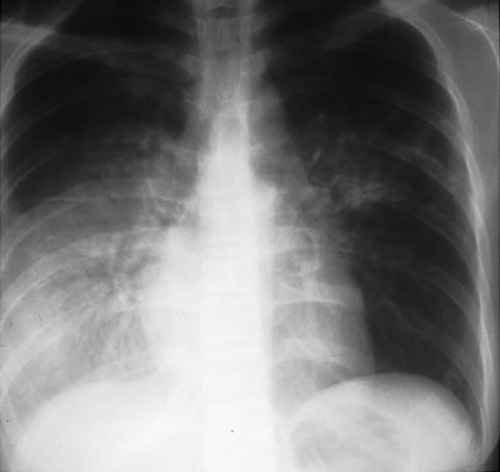

Затемнение в правой нижней части у больного с туберкулезом легких и сахарным диабетом

Сахарный диабет |

При неконтролируемом сахарном диабете показатель относительного риска от 2 до 4. |

Рентгенография грудной клетки - Исследование первой линии при диагностике туберкулеза - Почти всегда отмечаются патологические изменения на рентгенограмме у иммуноскомпроментированных лиц. К типичным изменениям относятся фиброзно-очаговые затемнения в верхних долях с кавернами или без них - Нетипичный легочный рисунок может сопровождаться затемнением в средний или нижних долях, прикорневой или паратрахеальной лимфаденопатией или плевральным выпотом - Специалисты утверждают, что атипичные изменения на рентгенограмме являются скорее следствием иммуносупрессии, чем первичного туберкулеза - ВИЧ статус обуславливает лимфаденопатию, выпот, вовлечение нижних долей легких и милиарный рисунок; при этом каверны обнаруживаются реже. Отметим, что у больных с прогрессирующей ВИЧ инфекцией рентгенограмма может быть нормальной |

- Характерные отклонения при туберкулезе - Нехарактерные отклонения при туберкулезе - Норма |